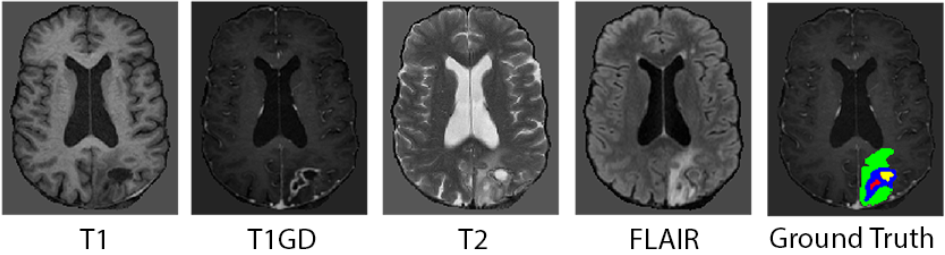

Each subject has four 3D MRI modalities including T1, T1Gd, T2, and FLAIR, as illustrated in Figure 2. These modalities provide complementary anatomical and pathological information: T1 offers structural detail, T1Gd highlights enhancing tumor regions, T2 captures edema, and FLAIR visualizes periventricular signal abnormalities by suppressing cerebrospinal fluid. The ground truth segmentations define four primary tumor subregions: enhancing tissue (ET), non-enhancing tumor core (NETC), surrounding non-enhancing FLAIR hyperintensity (SNFH), and resection cavity (RC). A fifth composite label, whole tumor (WT), is defined as the union of ET, NETC, and SNFH, and serves as an aggregate measure for overall segmentation performance. ET captures regions of active tumor and nodular enhancement; NETC denotes necrotic or cystic components within the tumor; SNFH includes edema, infiltrative tumor, and post-treatment signal abnormalities; and RC encompasses recent or chronic surgical cavities typically containing fluid, blood, or other proteinaceous materials [de20242024]. The challenge dataset, provided during the 2024 BraTS Challenge, consists of 1350 labeled post-treatment glioma cases and 188 unlabeled cases. For model development and evaluation, the 1350 labeled cases are randomly split into 1080 training, 135 validation, and 135 test samples using an 8:1:1 ratio. In addition, a post-challenge dataset, released after the 2024 BraTS Challenge and made available on the official website, contains 271 newly labeled post-treatment cases and serves as an additional test set.

Refer to caption

Figure 2: Example slices from the four MRI modalities and the ground-truth segmentation. For the truth labels, red is NETC, green is SNFH, blue is ET, and yellow is RC.